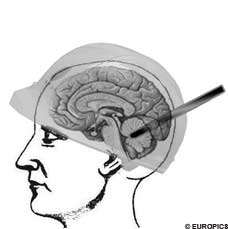

중국 충칭시의 한 곳에서 건설업자로서 일하고 있던 35살의 주 치앙구라는 남성은

긴급하게 뒷통수를 손으로 잡고 응급실로 후송되었다.

일을 하고 있던 도중에 하늘에서 갑자기 철창이 떨어지더니 이 남성의 뒷통수에 꽂혀 버린것이다.

아주 깊숙히 관통을 한 상황이라서 고통 조차 느낄 틈도 없었다고..

병원에 후송되어서 수술을 받았지만 경과를 더 지켜봐야 한다고 한다.